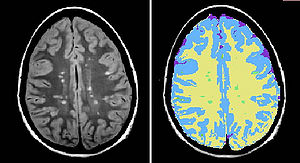

Potential of Diffusion Tensor Imaging and Relaxometry for the Detection of Specific Pathological Alterations in Parkinson's Disease (PD)

Publication: PLoS One. 2015 Dec 29;10(12):e0145493. PMID: 26713760 | PDF Authors: Esterhammer R, Seppi K, Reiter E, Pinter B, Mueller C, Kremser C, Zitzelsberger T, Nocker M, Scherfler C, Poewe W, Schocke M. Institution: Department of Radiology, University Hospital, Innsbruck Medical University, Innsbruck, Austria. Background/Purpose: The purpose of the present study was to evaluate the potential of multimodal MR imaging including mean diffusivity (MD), fractional anisotropy (FA), relaxation rates R2 and R2* to detect disease specific alterations in Parkinson's Disease (PD). We enrolled 82 PD patients (PD-all) with varying disease durations (≤5 years: PD≤5, n = 43; >5 years: PD>5, n = 39) and 38 matched healthy controls (HC), receiving diffusion tensor imaging as well as R2 and R2* relaxometry calculated from multi-echo T2*-weighted and dual-echo TSE imaging, respectively. ROIs were drawn to delineate caudate nucleus (CN), putamen (PU), globus pallidus (GP) and substantia nigra (SN) on the co-registered maps. The SN was divided in 3 descending levels (SL 1-3). The most significant parameters were used for a flexible discrimination analysis (FDA) in a training collective consisting of 25 randomized subjects from each group in order to predict the classification of remaining subjects. PD-all showed significant increases in MD, R2 and R2* within SN and its subregions as well as in MD and R2* within different basal ganglia regions. Compared to the HC group, the PD≤5 and the PD>5 group showed significant MD increases within the SN and its lower two subregions, while the PD≤5 group exhibited significant increases in R2 and R2* within SN and its subregions, and tended to elevation within the basal ganglia. The PD>5 group had significantly increased MD in PU and GP, whereas the PD≤5 group presented normal MD within the basal ganglia. FDA achieved right classification in 84% of study participants. Micro-structural damage affects primarily the SN of PD patients and in later disease stages the basal ganglia. Iron contents of PU, GP and SN are increased at early disease stages of PD. Funding:

The regions-of-interest (ROIs) were manually drawn by an experienced radiologist by using the b 1000 images, averaged for all measured directions, the FA maps and the proton-density weighted images. For that purpose, the maps of ADC, FA, R2 and R2* as well as the proton-density weighted images were first co-registered. The ROIs were segmented by syncing the b 1000 images, averaged for all measured directions, the FA maps and the proton-density weighted images in ImageJ. The ROIs were stored in the ROI manager and transferred to the co-registered maps. The segmented brain regions were highlighted in different colors: CN—black; PU—red; GP—green; TH—white; SN—blue; CC—cyan. The diffusion-weighted images, the R2 and R2*-weighted maps were transferred to the 3D Slicer software in order to co-register the R2 and the R2* maps as well as the MD and the FA maps |